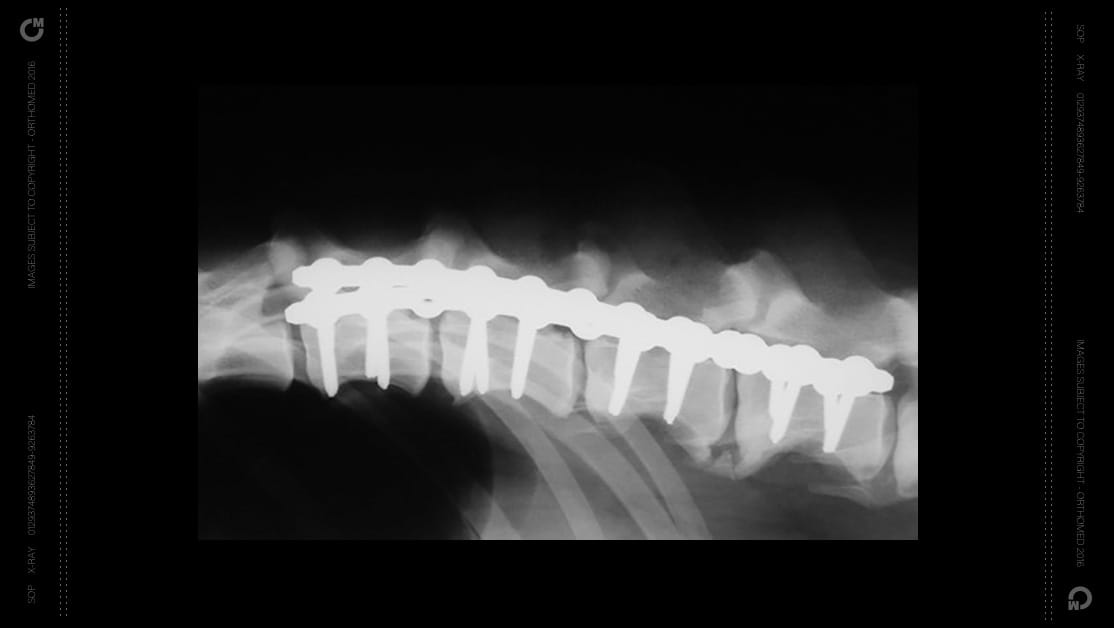

The SOP™ (String of Pearls) system is a strong and flexible mechanical locking plate system designed for fracture repair. The SOP™ plate consists of a series of cylindrical sections (‘internodes’) and spherical components (‘pearls’) that can be bent and twisted to suit almost every situation.

• Spinal Fractures

• Surgical spine distraction-fusion

Interlocking Plate

Flexible contouring on multiple planes with smooth uniform bends

The SOP™ can be contoured in six degrees of freedom; medial to lateral bending, cranial to caudal bending, and torsion. Properly performed, contouring results in bending or torsion at the internode, preserving the locking function of the pearl.